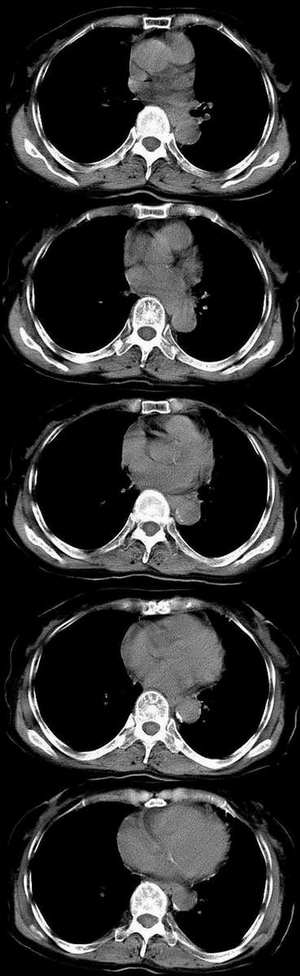

f73.反复胸痛、咳嗽5个月,加重1周入院。双肺呼吸音粗,闻及干湿性罗音。

慢支合并感染,肺间质纤维化,肺气肿。右肺斑片阴影还是考虑慢性感染性病变---结核不除外,因为支气管分叉下淋巴结增大。

图片上显示似乎右上支气管有阻塞,应倾向于肺癌。

2:右肺中叶肺癌伴左侧肋骨转移可能性大。

慢支炎,肺部感染,非局限性间质纤维改变,舌段可疑支气管扩张。中叶病变肿瘤待排。